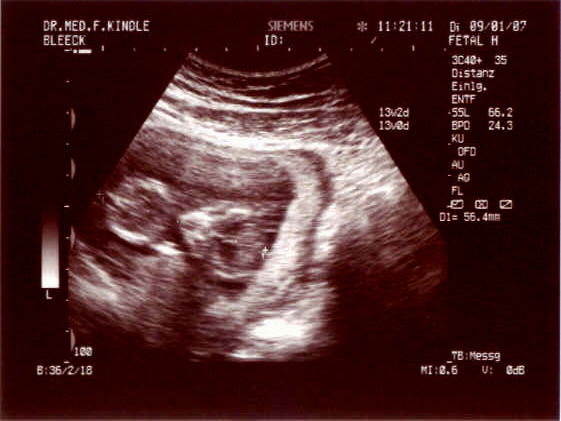

@all wollt ihr US Bilder sehen???

@Mella: Kann man zwar nicht viel auf dem US erkennen... aber ein bisschen schon ...

*neugierig frag* Was wird es denn? Rosa oder hellblau??? Oder wollt ihr es gar nicht wissen?